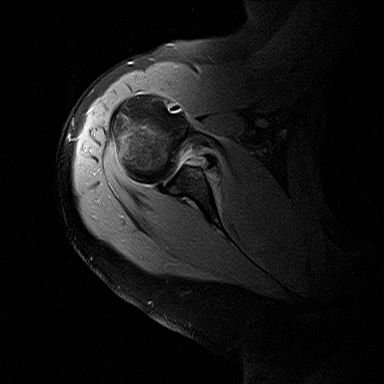

20 сентября 2012 в 08:11 Гілками Прикріплені файли (0 завантажити)

получилось снять скрин с МРТ